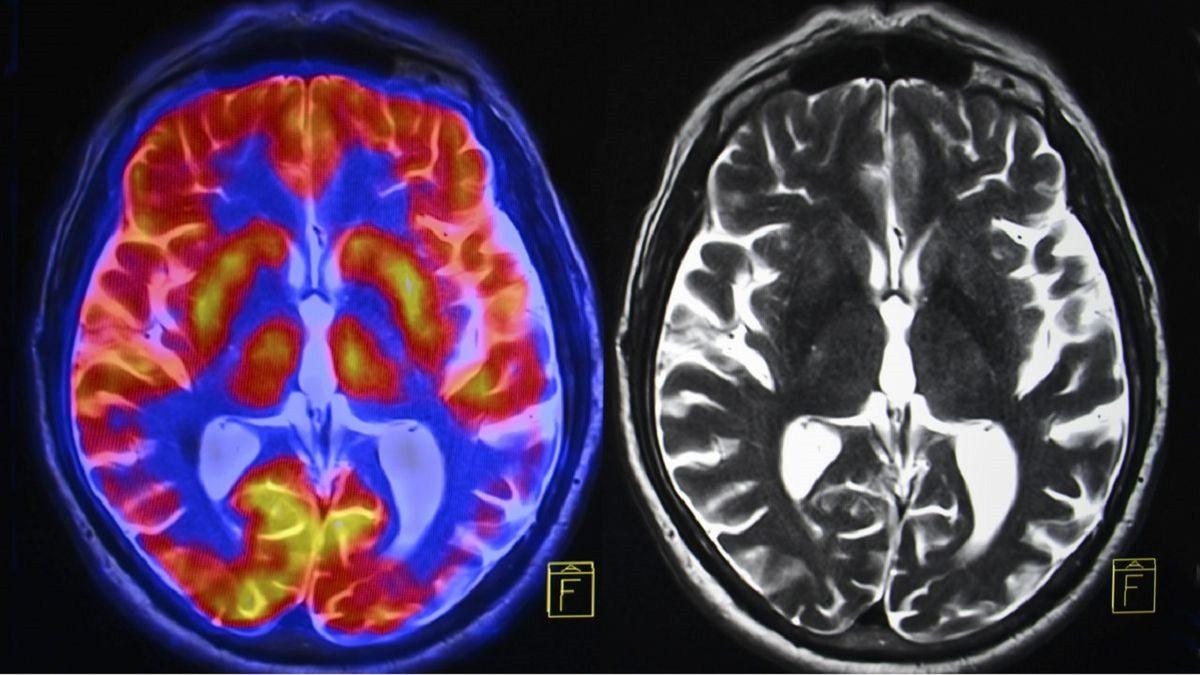

Bu konuda kalabalık denek grupları üzerinde yürütülmüş pek çok araştırma var. Örneğin Utah Üniversitesi'nden bir grup bilim insanının 2013 yılında 1011 katılımcı ile gerçekleştirdiği bir araştırmada yapılan beyin taramaları, kişinin kişiliğinden bağımsız olarak, beynin her iki tarafında da aktivitenin benzer olduğunu gösteriyor.

Farklı araştırmalarda ise beynin bir tarafına yüklenen daha mantıklı ve rasyonel olma eğilimi tamamen çürütülüyor. Yapılan incelemelerde, bir matematik işlemi yaparken beynin sağ ve sol kısımlarının eşit çalıştığı ve her iki bölgeye alınabilecek bir darbe durumunda aynı oranda matematiksel işlemlerde zorluklarla karşılaşacağı ortaya çıkıyor.